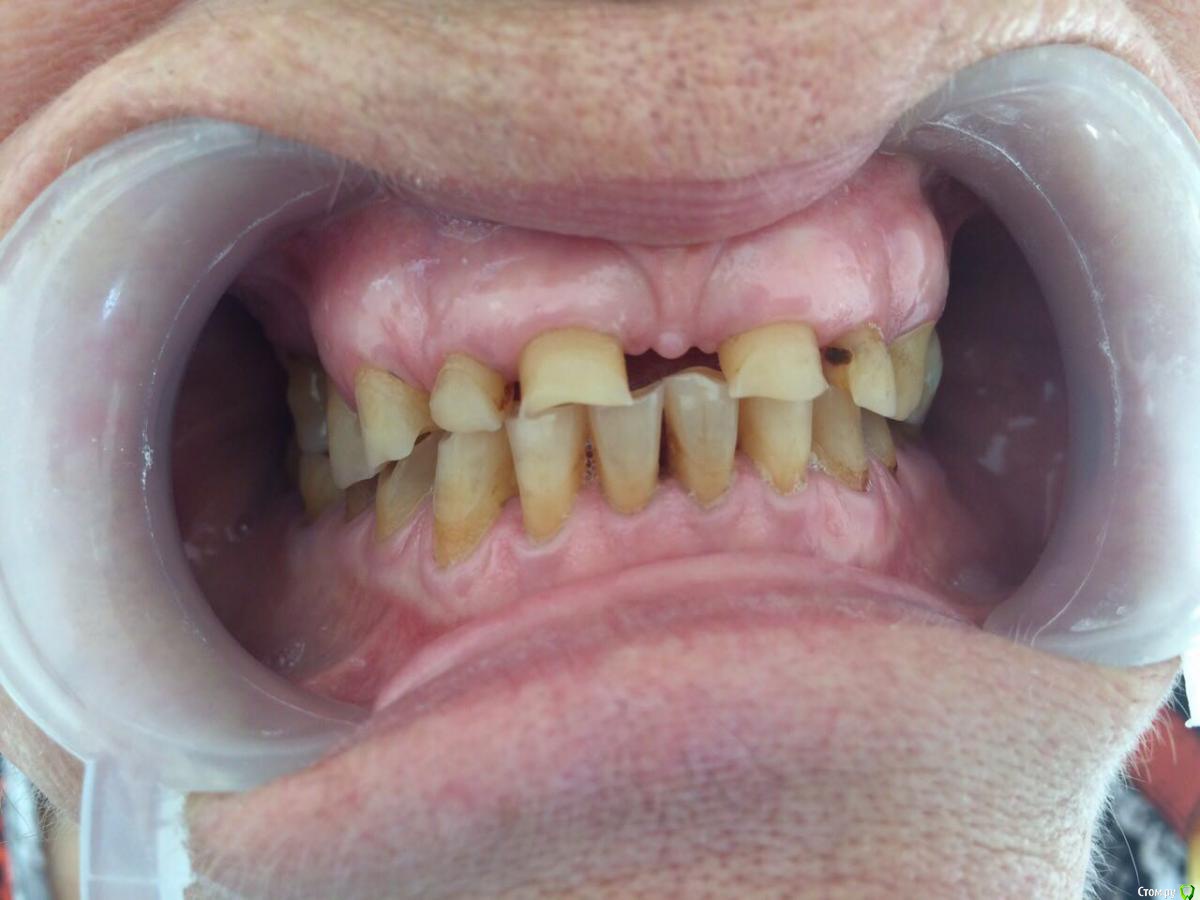

dr.Dre Опубликовано 31 июля, 2017 Поделиться Опубликовано 31 июля, 2017 Добрый вечер уважаемые коллеги ,пациентка 70 лет хочет металлокерамику,каналы очень склероризированые,как правильно протезировать при таком прикусе? Ссылка на комментарий

chervoncevdaniil Опубликовано 1 августа, 2017 Поделиться Опубликовано 1 августа, 2017 (изменено) пока пациентка хочет вверхИ что,вы хотите под такую анатомию нижних зубов ей сделать новый верх?Если хочет постоянные только верх,то на низ времянки на боковые,фронт хотя бы композитом подкорректировать,а дальше пусть хоть по зубу нижние в постоянные переводит,иначе ерунда,а не работа получится Изменено 1 августа, 2017 пользователем chervoncevdaniil 2 Ссылка на комментарий

bakagaidzin Опубликовано 1 августа, 2017 Поделиться Опубликовано 1 августа, 2017 (изменено) По уму надо делать все сразу,снять лицевую,определить ЦС,посчитать LVI и передать эти данные технику для ваксапа.а дальше уже в идеале конечно сделать мокап длительного,потом менять его на постоянные коронки..Но это все в идеале,сомневаюсь что на практике Вы это осуществите у 70 летней пациентки...плюс тут диастема огромная,нужна ортодонтия Изменено 1 августа, 2017 пользователем bakagaidzin 3 Ссылка на комментарий

Bobby Опубликовано 7 августа, 2017 Поделиться Опубликовано 7 августа, 2017 В данном случае, как правильно подметили, невозможно сделать один зубной ряд, не проводя реконструкцию антагонистов. Ссылка на комментарий